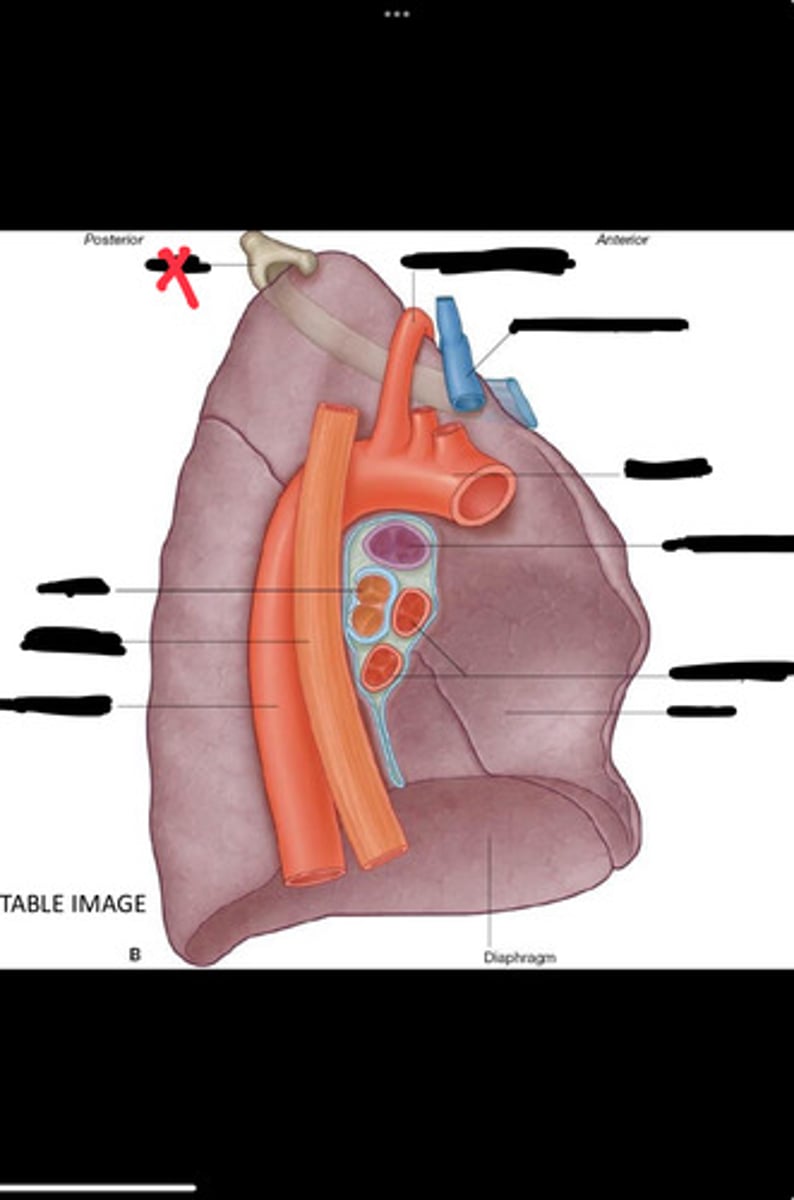

Diaphragm

Inferior vena cava

Superior vena cava

Subclavian vein

Right bracheocephalic vein

Subclavian artery

Esophagus

Bronchus

Rib 1

Left subclavian artery

Left brachiocephalic vein

Aortic arch

Pulmonary artery

Pulmonary vein

Heart

Left brachiocephalic vein

Azygos vein

Esophagus

Bronchus

Fibrous pericardium

Parietal layer of serous pericardium

Pericardial cavity

Visceral layer of serous pericardium

Junction between fibrous pericardium and adventitia

Heart

Thoracic aorta

Rib 1

Pulmonary artery

Bronchus to superior lobe